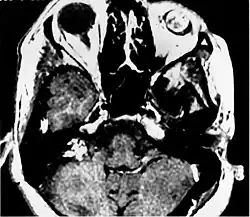

Ośrodkowy układ nerwowy

U wielu pacjentów pierwszym objawem choroby jest wystąpienie zmian narządowych w ośrodkowym układzie nerwowym o charakterze naczyniaków zarodkowych. Najczęstsze (75%)[3] są w móżdżku (haemangioblastoma cerebelli); poza móżdżkiem, guzy tego typu lokalizują się także w rdzeniu przedłużonym (haemangioblastoma medullae oblongatae) i rdzeniu kręgowym (haemangioblastoma medullae spinalis). Objawy wywoływane przez guza zależą od jego lokalizacji i rozmiarów. Guzy móżdżku początkowo nie dają objawów; potem pojawiają się bóle i zawroty głowy, nudności i wymioty, objawy móżdżkowe, dysmetria i porażenie nerwu IX. Naczyniak zarodkowy rdzenia przedłużonego objawia się z reguły bólami głowy, nudnościami, wymiotami, upośledzeniem czucia i motoryki, zaburzeniami połykania, oddychania. Naczyniaki zarodkowe rdzenia kręgowego dają bardzo niespecyficzny zestaw objawów obejmujący bóle, niedowłady, zaniki mięśniowe, zaburzenia czucia głębokiego i/lub powierzchniowego. W obrębie rdzenia przedłużonego i rdzenia kręgowego może rozwinąć się jamistość rdzenia (syringomyelia).